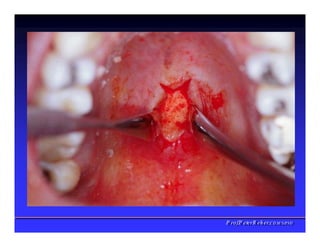

Face interna dos Lábios

✓Freios Labial

superior

✓Freio Labial

inferios

✓Bridas

Musculares